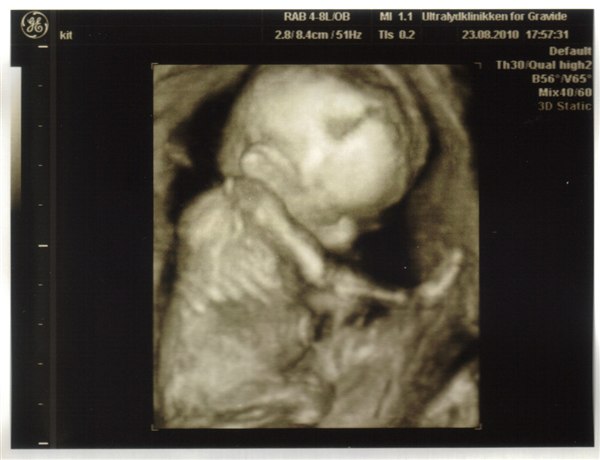

Jeg bestilte tid til en kønsscanning i Hobro igår, så vi skal afsted torsdag i næste uge (d. 2-9). Min mand og to andre børn er nysgerrige, og det er jeg også blevet efterhånden, selvom jeg fra starten gerne ville vente til fødslen!

Jeg havde jo også nævnt, at vi måske ville tage børnene med til MD-scanningen, men vi kunne jo ikke være sikre på, at de ville få lov til at komme med ind. Nu er vi ude ovre det problem, for nu tager vi dem med til kønsscanningen i stedet!

Er megaspændt nu - og synes der er riiiigtig lang tid til på torsdag.

Pia 17+1